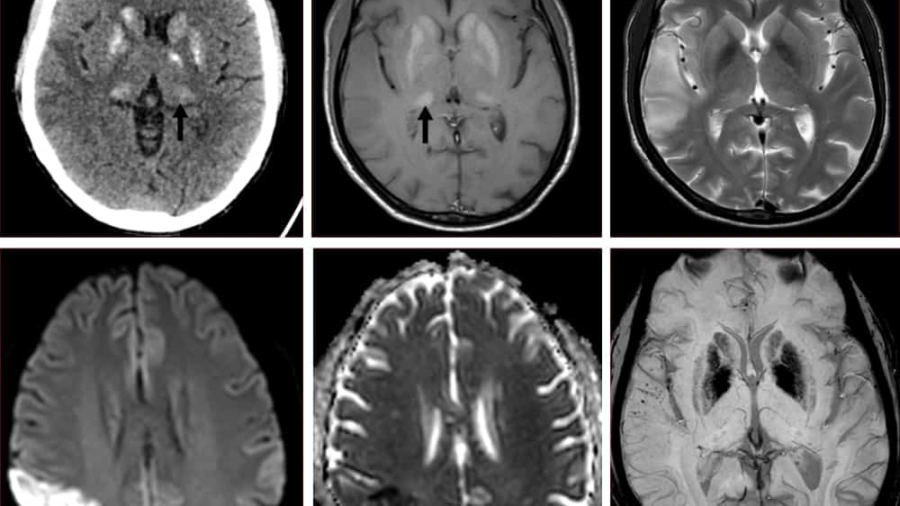

45 year old man

K/C/O Type II DM/Hypertension

Presented with bifrontal headache associated with vomiting

Visual hallucinations

Imbalance while walking

Patient developed multiple episodes of seizures, became aggressive and restless during the hospital stay